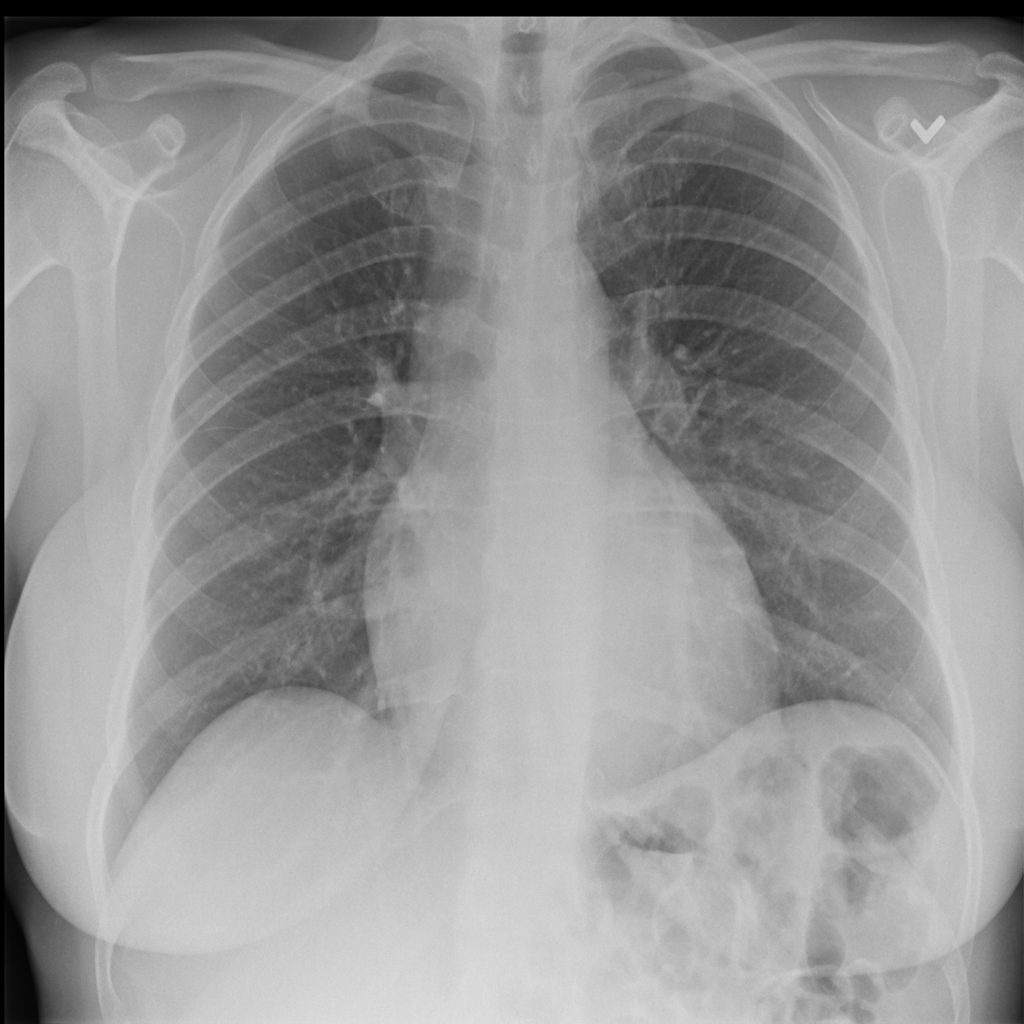

We conclude our analysis with consideration of the ChestXray-14 [RIZ+17] dataset. This dataset contains frontal X-ray images labeled with 14 different conditions. ChestXray-14 is a multi-label tagging task (i.e., a single image can have more than one condition), so we treat each condition as its own binary problem. In this section, we focus on the condition Effusion. Results on other conditions can be found in Appendix C.3.

The trained SVM identifies visually distinguishable failure mode directions in latent space. As shown in Figure 11, the representative images flagged by this SVM as most incorrect are blurrier and less bright. Moreover, this trend is not reflected by the least confident images, indicating that our framework is isolating a different trend than the one corresponding to ordering the images by base model confidence.

In fact, we find that the SVM may be picking up on the position in which the exam was conducted. While the majority of the X-rays are Posterior-Anterior (PA) radiographs, a little over a third are Anterior-Posterior (AP). PA radiographs are usually clearer, but require the patient to be well enough to stand [TB20]. Examples of AP and PA radiographs from the dataset can be found in Appendix C.3.

As shown in Table 13, the SVM for the class “no effusion” flags a large number of the AP radiographs as incorrect. This indicates that the model might indeed rely on the position in which the radiograph was taken to predict whether the patient was healthy. Moreover, the SVM selects the AP examples more consistently than ordering the radiographs by the base model’s confidence (Figure 13).